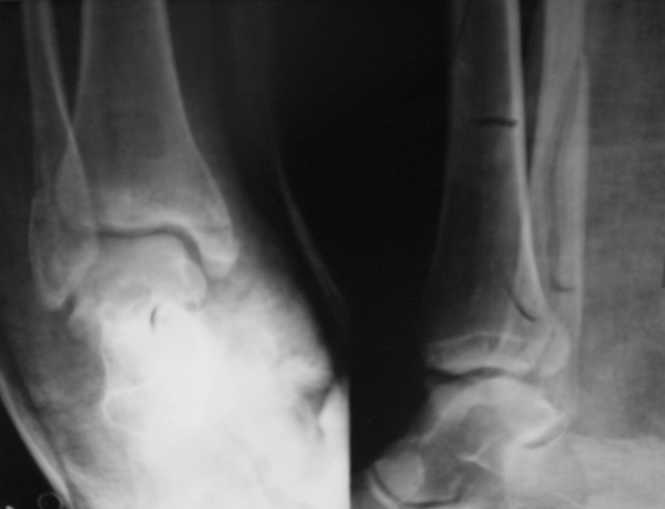

Вот рентгенконтроль на 7-е сутки после репозиции.

Стандартными снимками считается прямая, боковая и мортиз!!!, а так трудно гадать, насколько потеря длины малоберцовой. На боковом снимке не сопоставленный перелом медиальной лодыжки и перелом заднего края без смещения.

Очень жаль, что Вы так считаете и не прислушались к мнениям уважаемых коллег. Проблема этого голеностопного сустава не в "висячей" внутренней лодыжки, а ротированной и, возможно, укороченной малоберцовой кости. На снимках подвывиха как-буд-то бы нет, но таран ротирован и это в дольнейшем будет причиной раннего артроза.